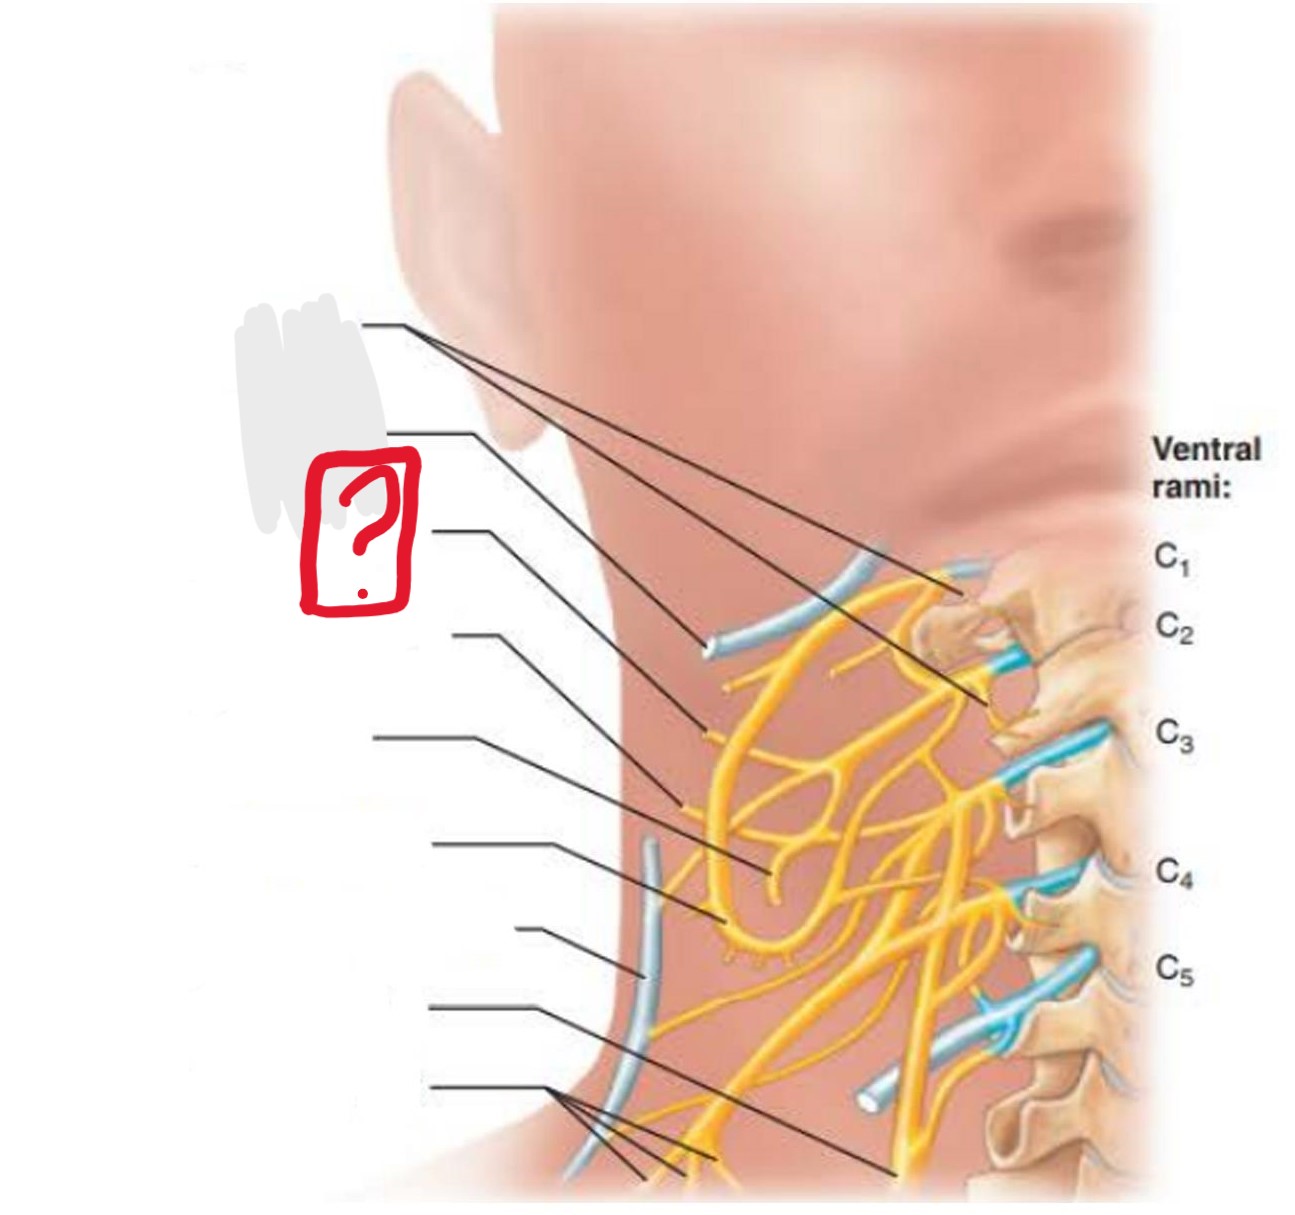

cervical plexus

C1-C4

segmental branches

hypoglossal nerve (12)

lesser occipital nerve

greater auricular nerve

transverse cervical nerve

ansa cervicalis

accessory nerve (11)

phrenic nerve

supraclavicular nerves